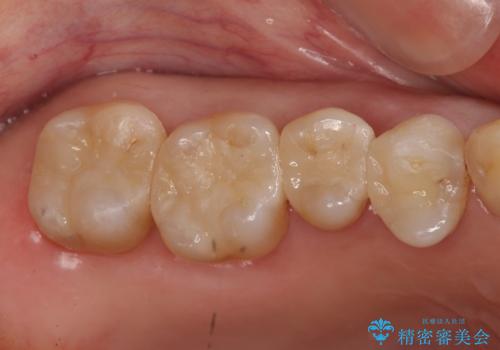

- 虫歯治療を希望して来院。

保険適用の銀色のつめもののやり替えを行いました。

- 30.8万円(右上4567 emaxプレスインレー 7万円x4本)費用は治療当時の料金となります

自由診療のインレーの歯型には、シリコンを使用しています。また、処置時には8倍の拡大鏡を用いて、精密に治療しております。